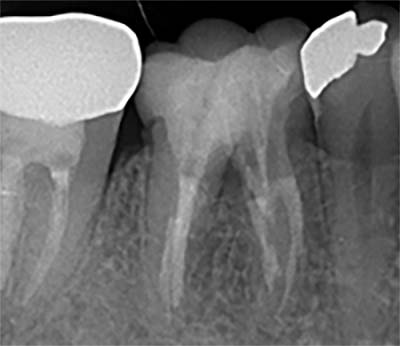

CT撮影で根の状態を“立体的”に診断

レントゲンは2Dですが、CT(3D)では病変の広がり・分岐・湾曲・破折線を正確に把握できます。

特に、

- 他院で治らなかった根尖病変

- 大臼歯の複雑な形態

- 器具破折の有無

- 嚢胞の存在

などはCTでしか判断できません。“診断の精度=治療の成功率” であるため、CT診断は必須です。